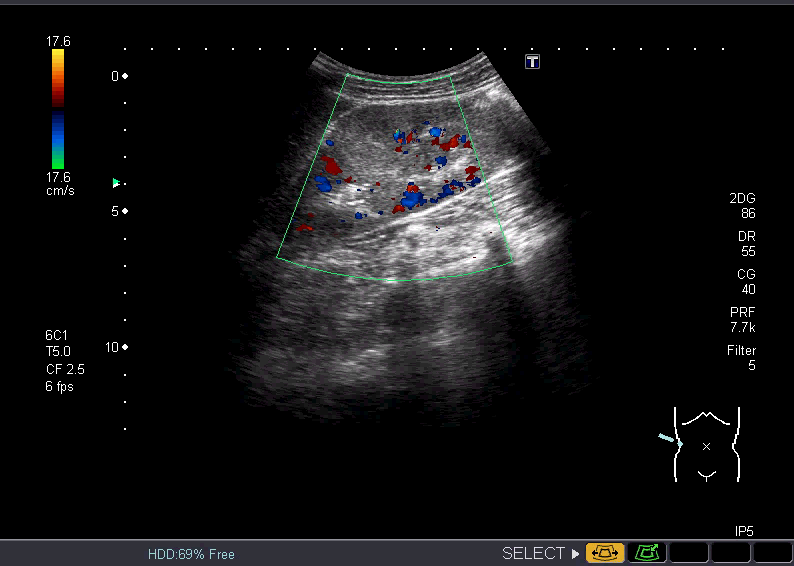

特に熱の原因はわからないまま、右腎の皮質中央に高エコーの腫瘤を発見

⇓画像になります。

採血では、白血球・CRP 高値。尿検査:異常なし。

エコーでは腎実質内に高エコー腫瘤として描出されカラードプラにて無血管領域として描出される